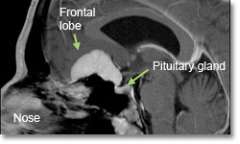

Location - Olfactory Groove and sella (bony space where the pituitary gland is situated)

Common Symptoms - Loss of smell (anosmia), subtle personality changes, mild difficulty with memory, euphoria, diminished concentration, urinary incontinence, visual impairment.

- Magnetic resonance imaging (MRI) scans effectively detect most meningiomas and are best at displaying details of the brain.

Endoscopic removal of meningiomas through the nose

- olfactory groove meningiomas

- tuberculum sella meningiomas

- sellar meningiomas